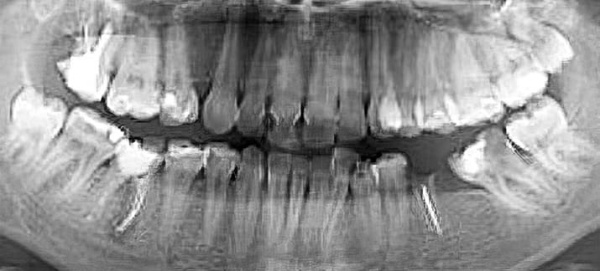

— На ортопантомограмме (см. рис. 2) видно, что зачатки третьих премоляров заложены глубоко, зачатки зубов 1.8 и 2.8 расположены близко к верхнечелюстным пазухам, 4.8 — к нижнечелюстному каналу. Чтобы удалить такие зубы, требуется весьма сложное травматичное вмешательство, как правило, под общим наркозом. При этом показаний для удаления нет, — прокомментировал Яков Тимчук.

Рисунок 2. Ортопантомограмма 15-летнего пациента с глубоко заложенными зачатками 8-х зубов.

— Вот еще один пациент (см. рис. 3) с верхними «восьмерками», залегающими очень близко к верхнечелюстным пазухам, что несет большие риски при удалении. Иногда на удаление направляют пациентов с начинающими прорезываться «восьмерками», при этом показания к удалению отсутствуют, т. е. третьи моляры не препятствуют дистализации (см. рис. 4).

Рисунок 3. Ортопантомограмма 15-летнего пациента с глубоко заложенными зачатками 8-х зубов.

Рисунок 4. Ортопантомограмма пациентки 15 лет. Показаний к удалению «восьмерок» нет.